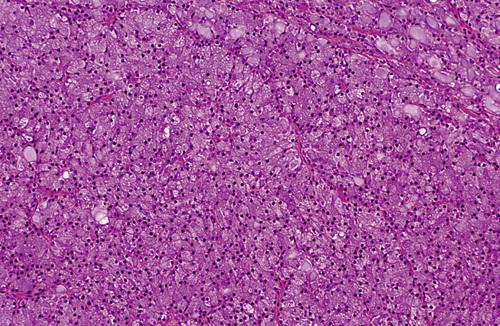

Chronic inflammatory infiltrate with associated acinar atrophy, ductal dilatation, and fibrosis.

chronic sclerosing sialadenitis